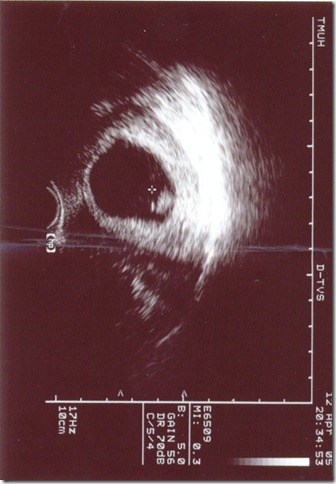

於是她帶著肚子裡的小p來給我探班,這真的是空前絕後僅此一次